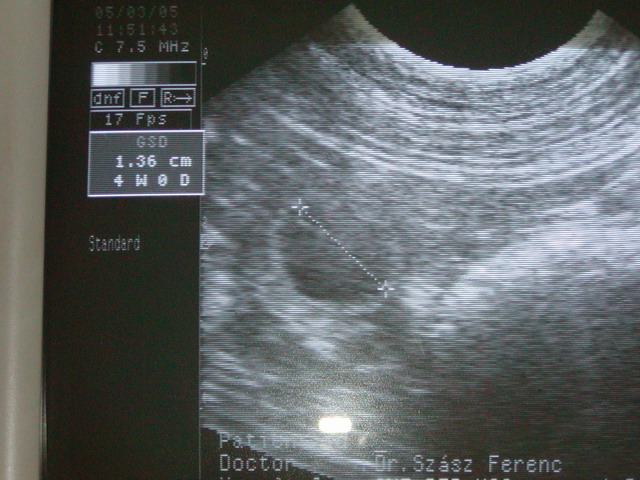

here we are with 21 days on the ultrasound-picture !